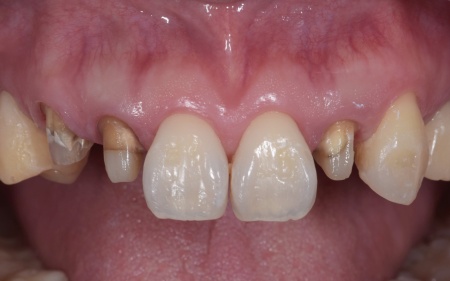

40代女性 矯正治療で噛み合わせを整えたあとセラミックの被せ物・詰め物で修復した症例

「左下の奥歯が欠けたのと、右上の差し歯が取れた」とご相談いただきました。

拝見したところ、左下と右上の歯はともに大きな虫歯があり、歯だけでなく被せ物を支える土台の部分にも影響が及んでいました。

さらに、ほかの歯に入っている詰め物や被せ物の周囲にも、過去に治療した部分に再び虫歯ができる二次カリエスが複数見つかりました。

また、噛み合わせを確認したところ、奥歯で噛み合わせた際に上下の前歯が当たらず隙間ができる開咬(かいこう)が認められました。